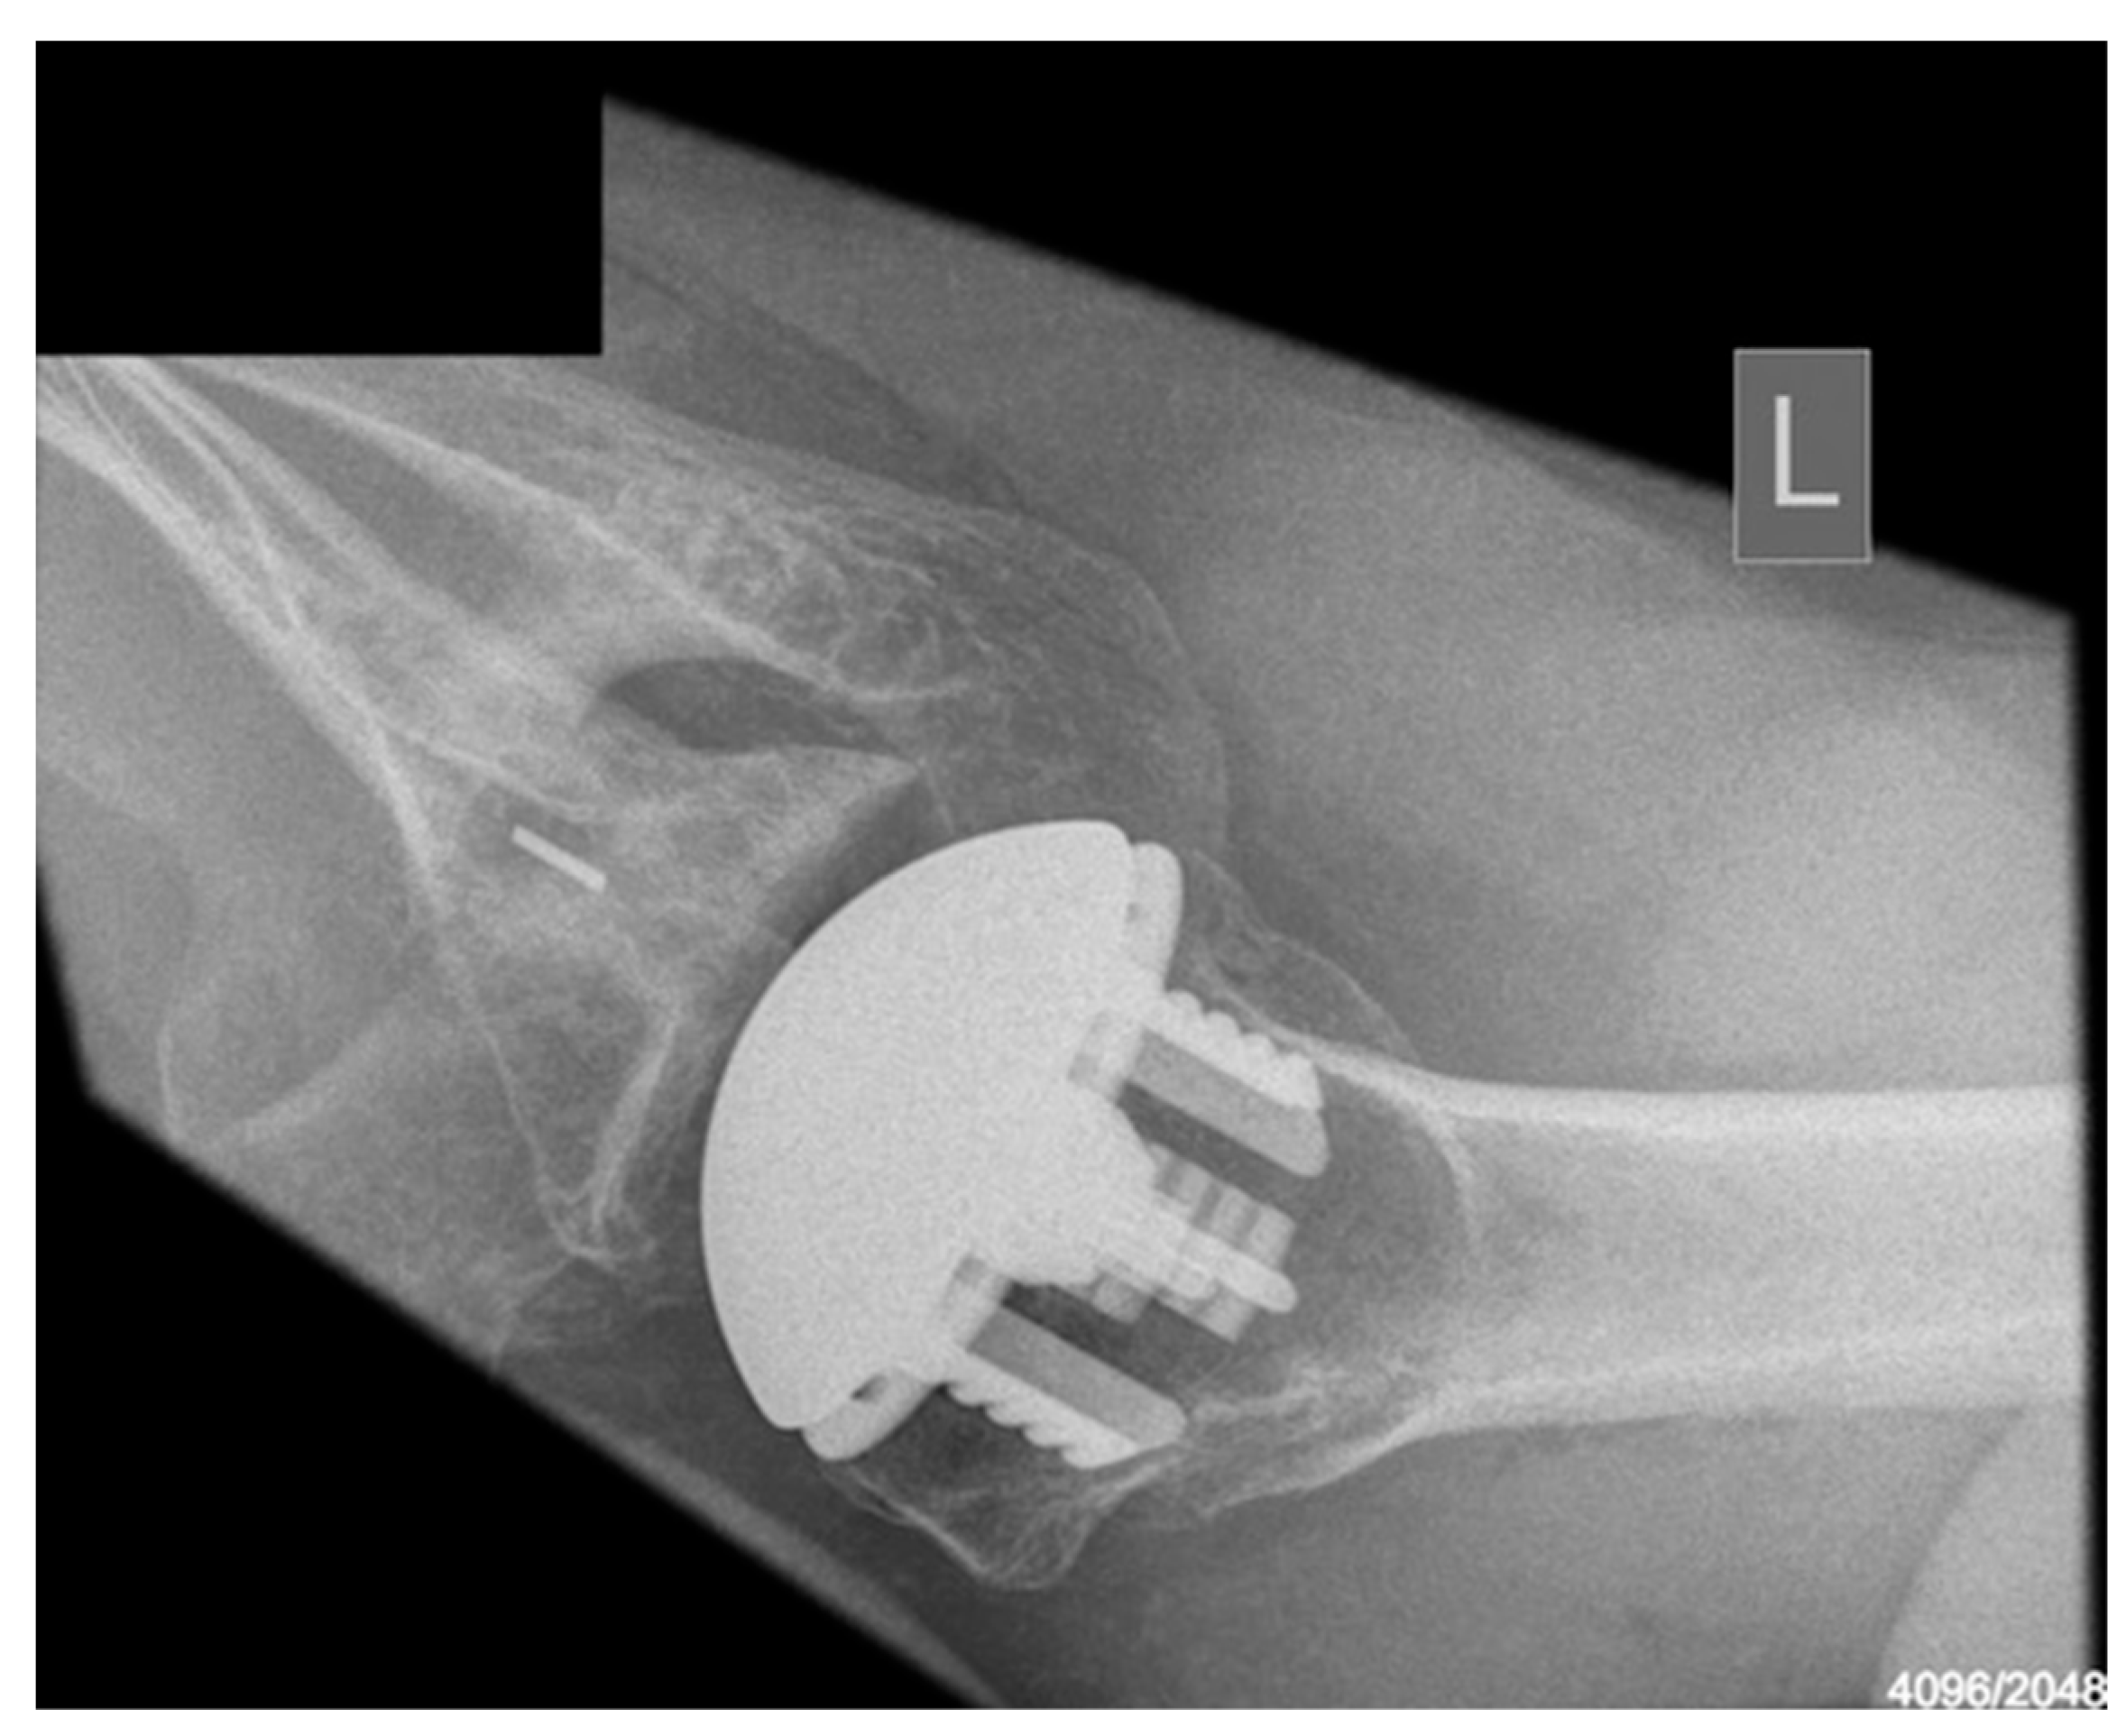

Radiological outcomes are outlined in Table 3. Twenty-six participants had radiographs available for review at a mean follow-up of 64 weeks. No component significantly loosened, migrated, or subsided. All glenoid components were grade 0. Ultimately, 21 of the 26 participants and 17 of 26 participants had anteroposterior and axillary views respectively available for review. For the humeral component, radiolucencies were minimal and located in zones 1, 5, 6, and 10. Figure 5 displays an anterior to posterior post-operative X-ray, and Figure 6 displays an axillary lateral post-operative X-ray showing the anchorpeg position.

Figure 5.

Anteroposterior post-op X-ray showing no overstuffing of the joint, 24-month post-operative. Female participant aged 62 years.